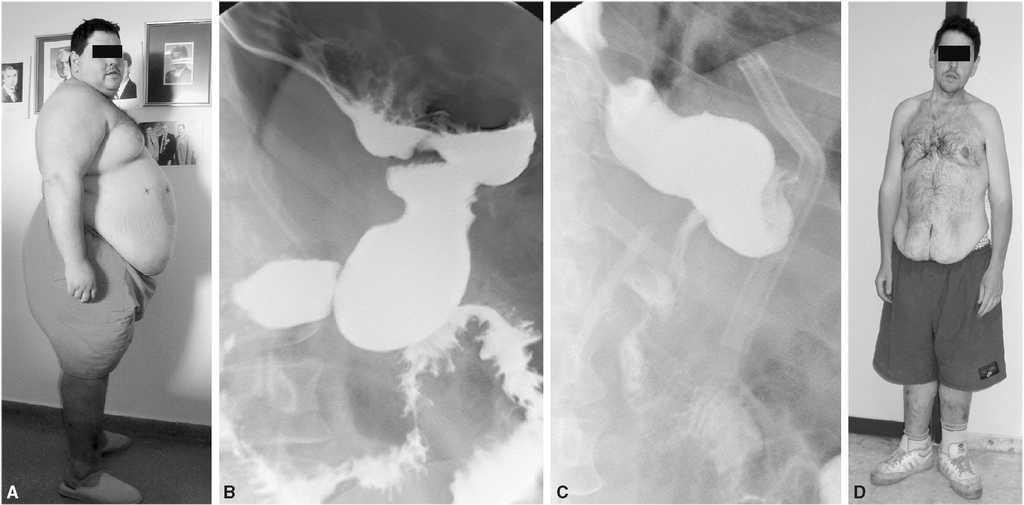

Fig. 1. A: estado preoperatorio del paciente 2. B: tránsito baritado del paciente 2 antes de realizar el segundo tiempo del CDL. C: tránsito baritado del paciente 2 después de realizar el segundo tiempo del CDL. D: estado final.

Varón de 32 años (IMC = 64) que fue intervenido en junio de 2004 mediante una GTL. Alcanzó una pérdida de peso máxima de 68 kg y un IMC de 42 a los 9 meses de la intervención estabilizando sus parámetros bariátricos. En marzo 2006 se indicó el segundo tiempo quirúrgico para completar el CDL, y una dilatación del remanente gástrico (fig. 1B) hizo que se considerara la realización de una RGTL sobre una sonda tutora de 32 Fr. La figura 1 muestra el tamaño final del tubo gástrico después de la regastrectomía tubular (C), y también el estado preoperatorio del paciente (A) y el resultado final (D).